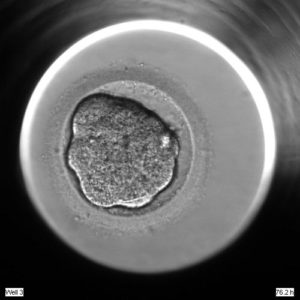

lab_005

2020.06.08

培養室

胚の評価について